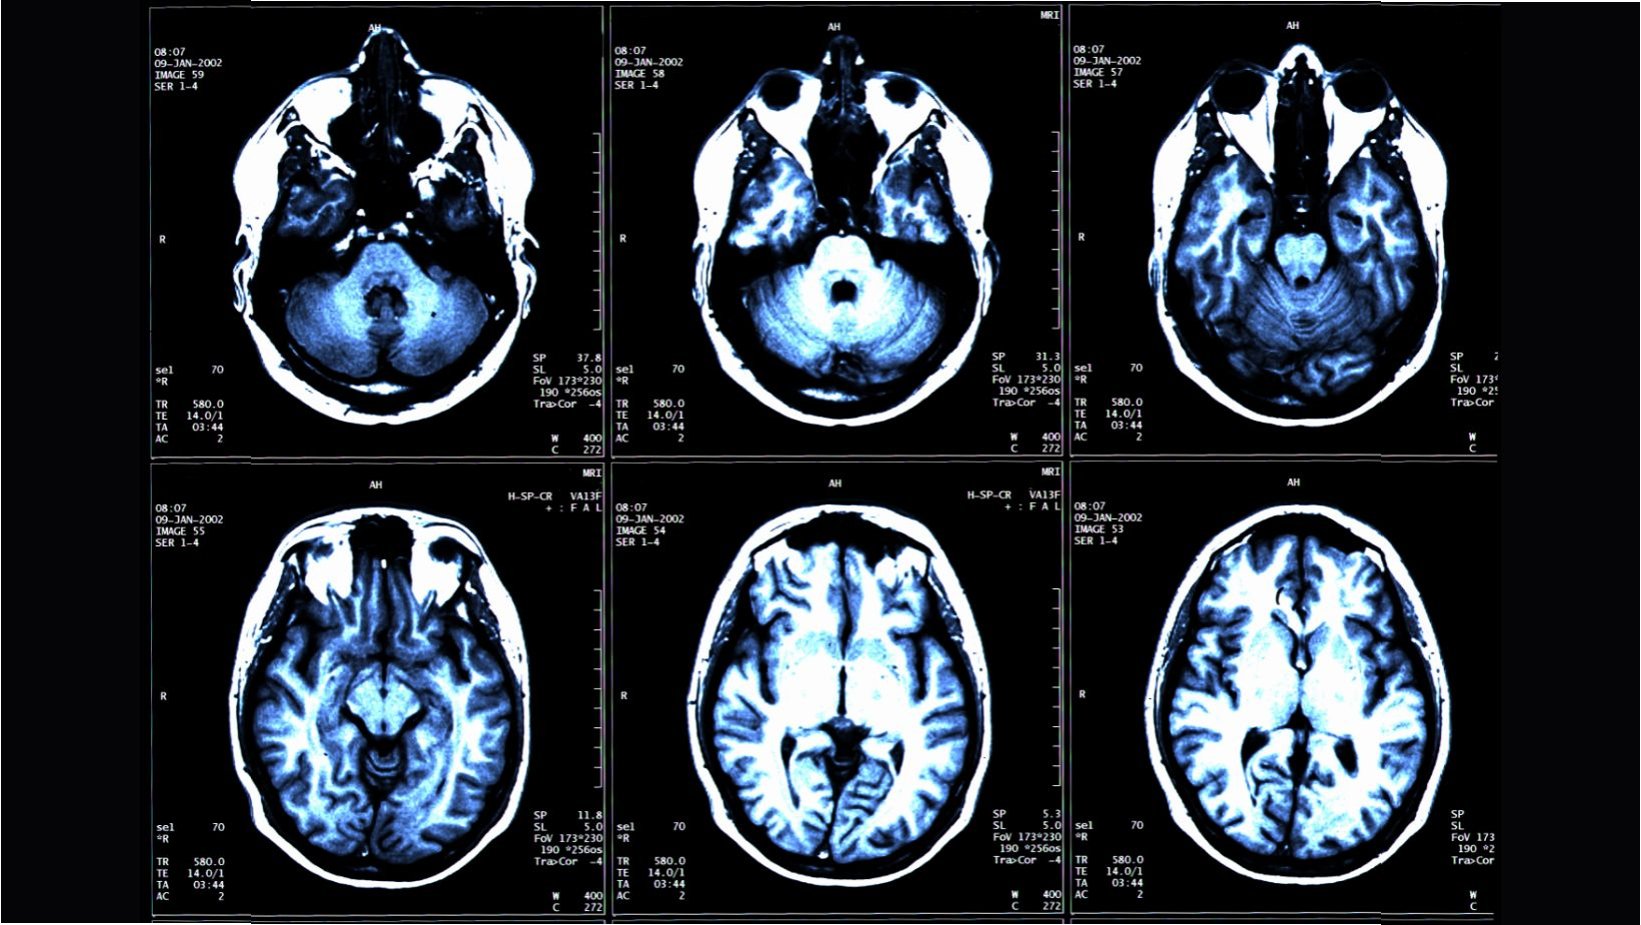

미국 워싱턴대 의대 사이러스 라지 박사팀은 북미영상의학회 연례 학술대회(RSNA 2025)에서 이 같은 연구 결과를 발표할 예정입니다. 연구팀은 전신 MRI를 통해 건강한 성인 1164명의 근육과 지방, 뇌 조직을 촬영하고, 인공지능(AI)으로 분석했습니다. 그 결과는 매우 흥미로운데요. 총근육량이 많을수록 실제 나이가 더 적고 뇌 MRI로 계산한 뇌 나이도 더 젊은 것으로 나타났습니다. 즉, 근육이 많을수록 뇌가 젊어진다는 것입니다. 이는 단순히 추측이 아닌, 과학적인 데이터로 증명된 사실입니다.